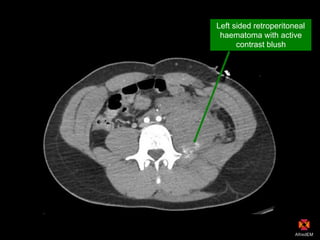

Left sided retroperitoneal

haematoma with active

contrast blush

CT findings

Psoas haematoma with active blush (L4/5)